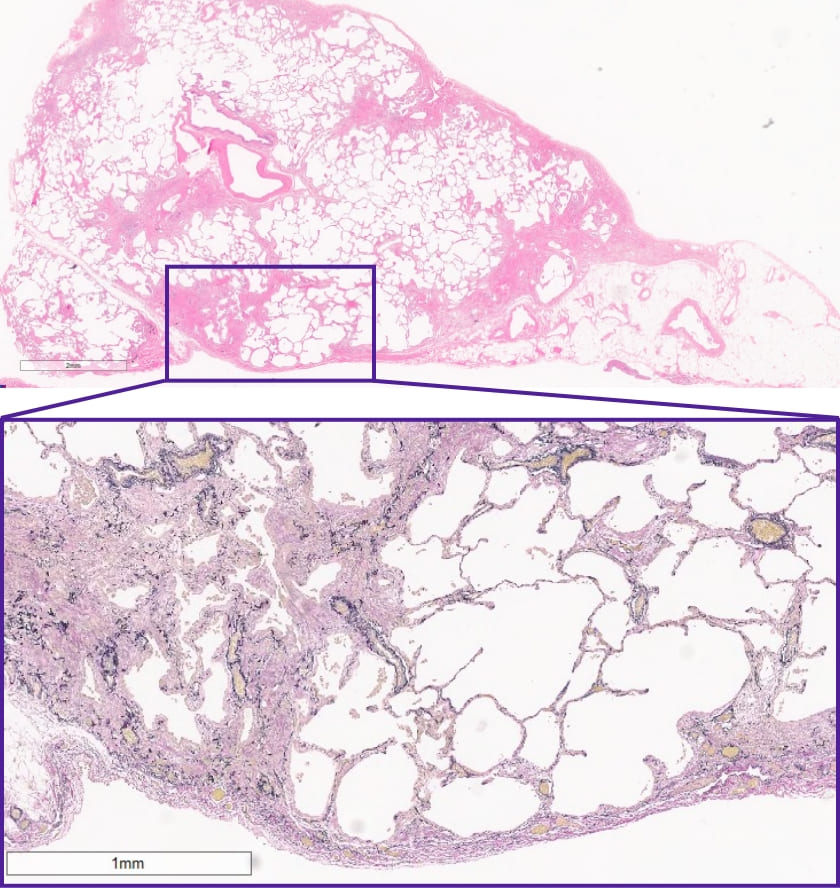

この症例の外科生検検体は?

DATA 1| X 線検査結果